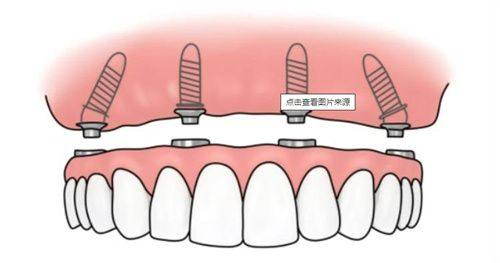

| All - on - 4全口种植 | 9.8万元起 | 4颗植体支撑全口牙,节省费用 |